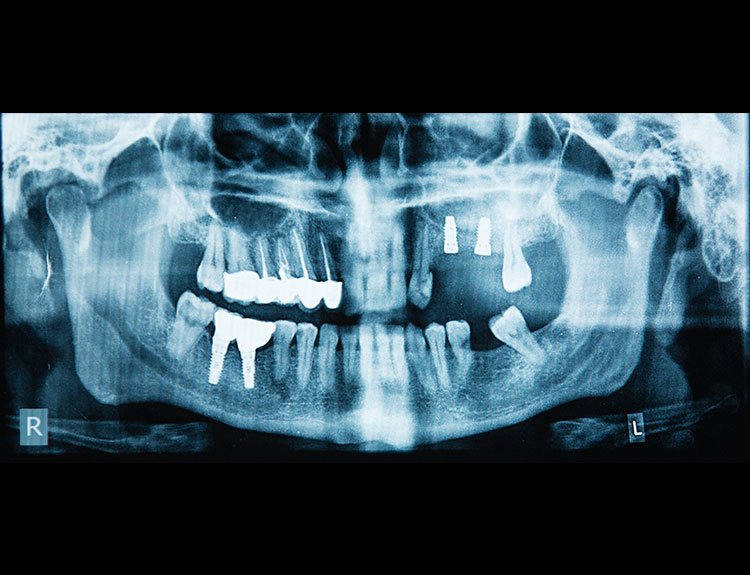

Dental implants are artificial tooth roots made of medical-grade titanium that are surgically placed into the jawbone. Once the implant integrates with the bone, a crown is fixed on top, giving you a strong, natural-looking replacement tooth.

If you are searching for reliable Dental Implants in Punjabi Bagh, Dental Que provides personalized solutions based on your oral health, bone condition, and smile goals.